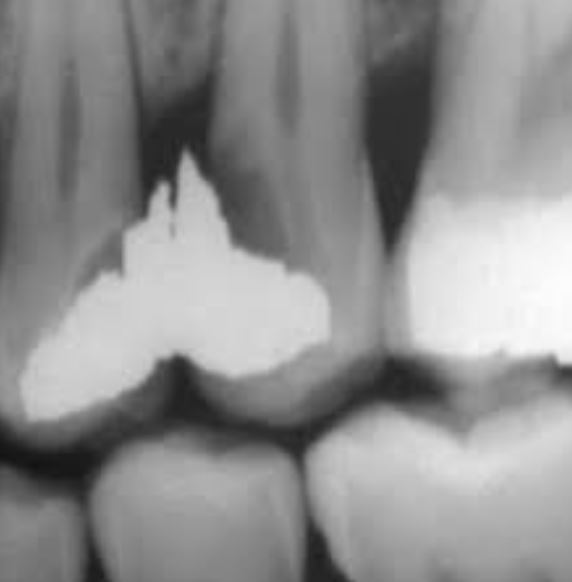

Le syndrome du septum interradiculaire : définition, diagnostic et prise en charge complète

1. Définition clinique du syndrome du septum interradiculaire Le syndrome du septum interradiculaire (parfois appelé syndrome du septum interdentai...